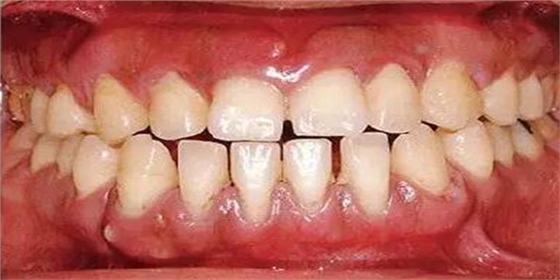

●45歲女性 慢性牙周炎(重度)口腔內(nèi)照片

45歲女性,曾經(jīng)接受過(guò)口腔衛(wèi)生指導(dǎo)和牙周治療,菌斑控制情況除去部分磨牙部位其余基本良好。牙周探診檢查結(jié)果為全頜牙周袋深4~6mm,同時(shí)X片檢查數(shù)據(jù)可看到全頜重度骨吸收。根據(jù)以上檢查數(shù)據(jù)可診斷出該患者為慢性牙周炎廣泛型(重度)。牙齦沒(méi)有嚴(yán)重浮腫,但可觀察到紅褐色腫脹。上頜前牙有前突。